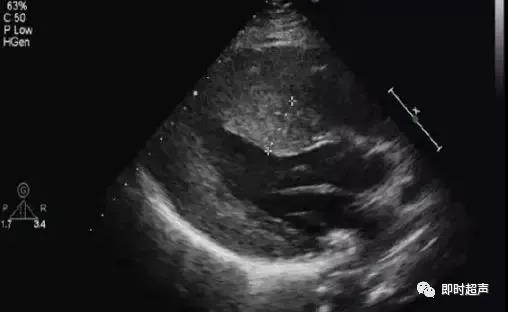

病例:女,73岁 胸闷、气逼、乏力

全心扩大,以左房、左室明显,右房右室稍增大,升主动脉内径及肺动脉内径增宽,主动脉瓣、二尖瓣回声稍增强增厚,开放可,关闭欠佳,余瓣膜形态回声可,开放可,室间隔及左室后壁厚度正常,室间隔运动搏幅明显减弱,左室后壁运动幅度略减弱,室壁运动不协调,房室间隔连续完整。